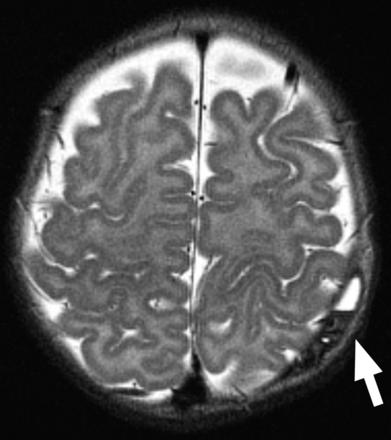

MR imaging of a 3-month-old patient found to have a bump on the head on physical examination. T2-weighted axial image shows an FFL within a cephalohematoma (arrow), confirmed to be within the bone on multiple planes and sequences (not shown).